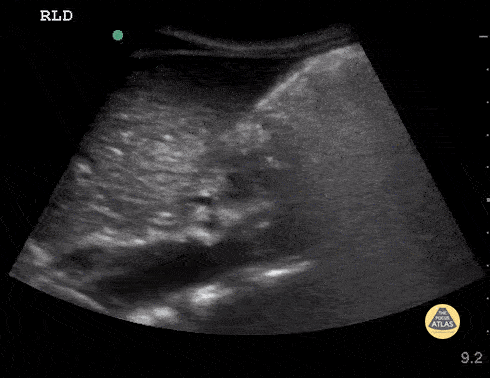

Ultrasound used to assess gastric content prior to procedural sedation. Sagittal view in the epigastric region using the curvilinear probe with the patient in the right lateral decubitus position. Probe indicator cephalad. The gastric antrum is seen in the upper right with heavily air-admixed content with dirty shadow obscuring deeper content. The liver is seen in the upper left and the aorta in the deep field. Contributor: Matthew Moake, MD PhD